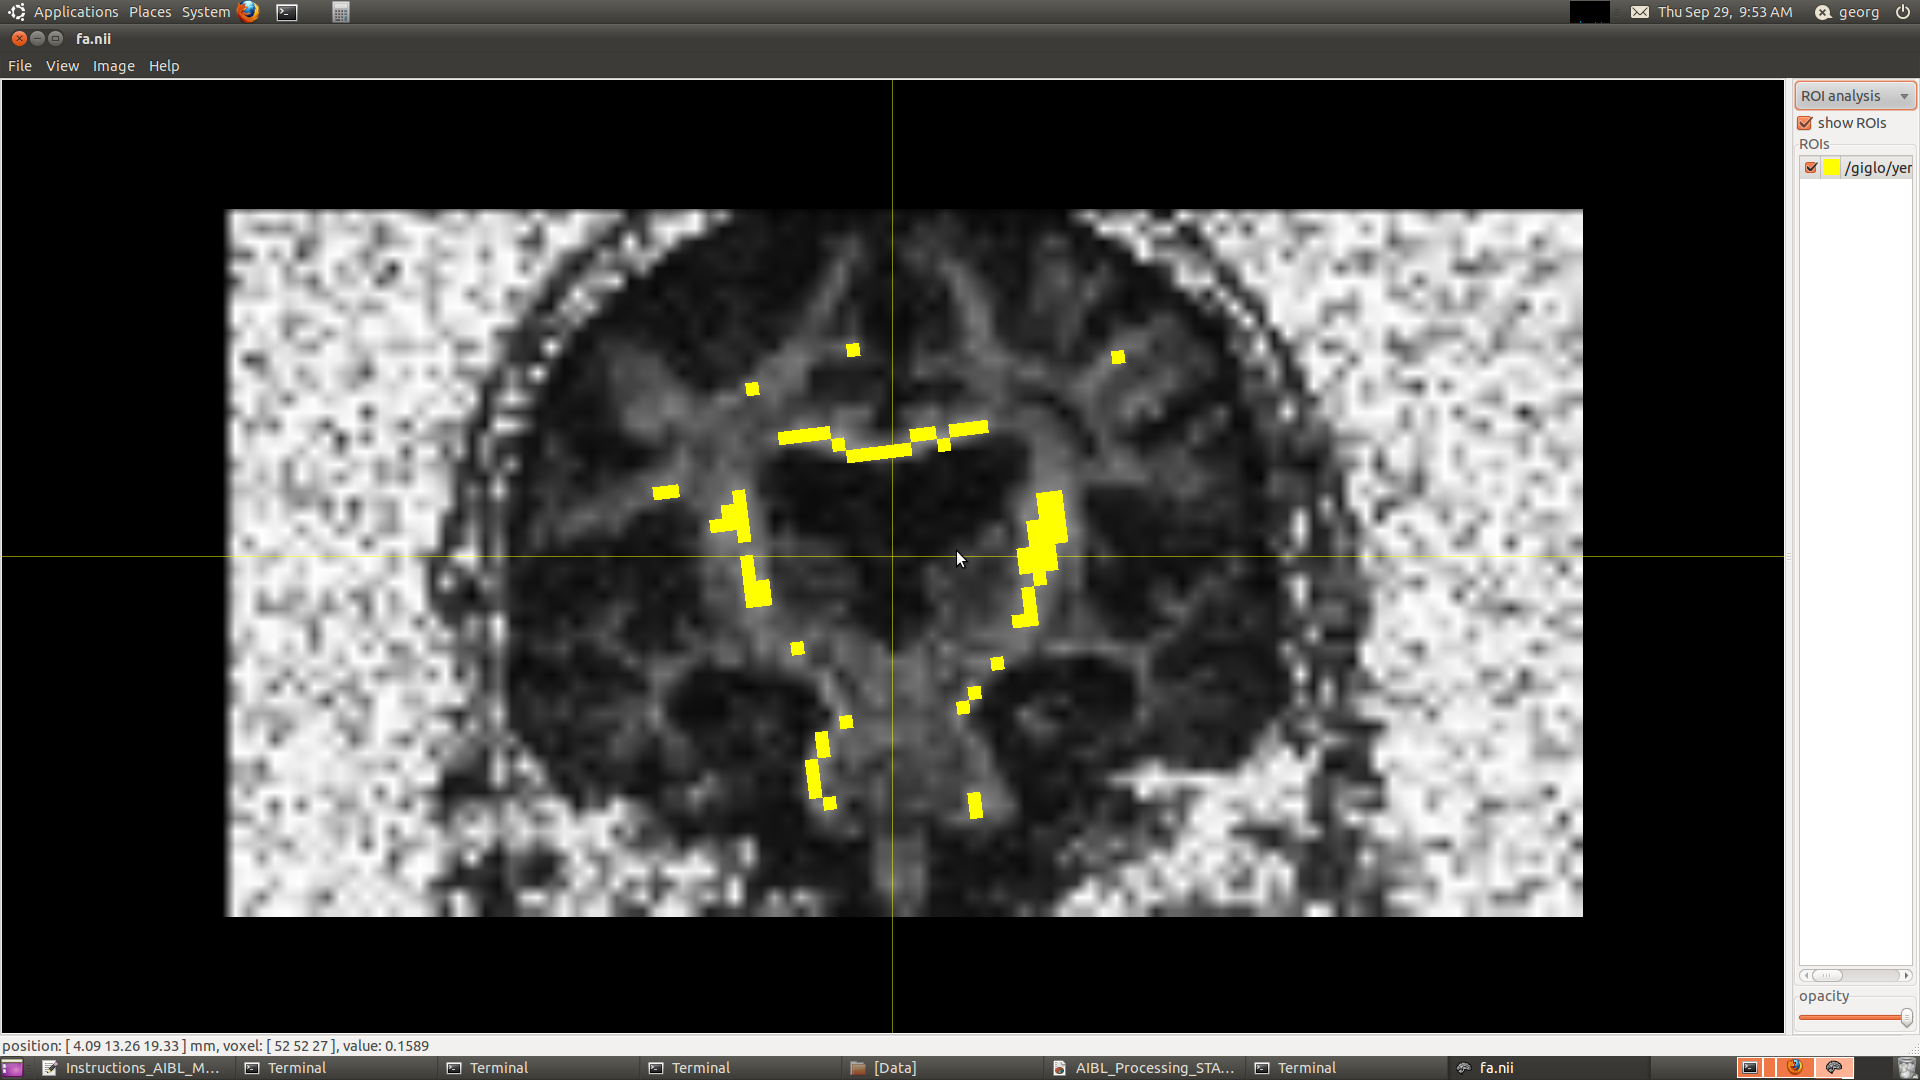

I'm having some trouble with the single fibre mask for one of my subjects; sf.mif is at an angle compared to FA and to rawdata (see attached screenshot).

$ mrconvert rawdata.mif -coord 3 0 - | threshold - - | median3D - - | median3D - - | erode - - | erode - - | erode - - | mrmult - fa.nii - | threshold - -abs 0.6 sf.mif